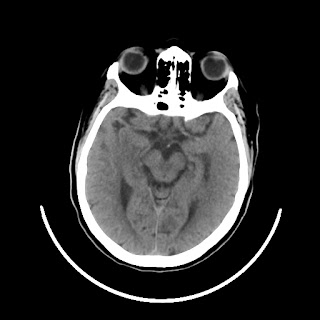

A 75 years old woman with DM-2 since 3 years

Patient O/E images:

C/O: Breathlessness X 2-3 day's

Vomiting 1-2 episode since last night

Cough X 2-3 day's

H/O: unconsiouness since few hour's at home around 10:30 pm

K/C: DM / HTN since 2-3 year's